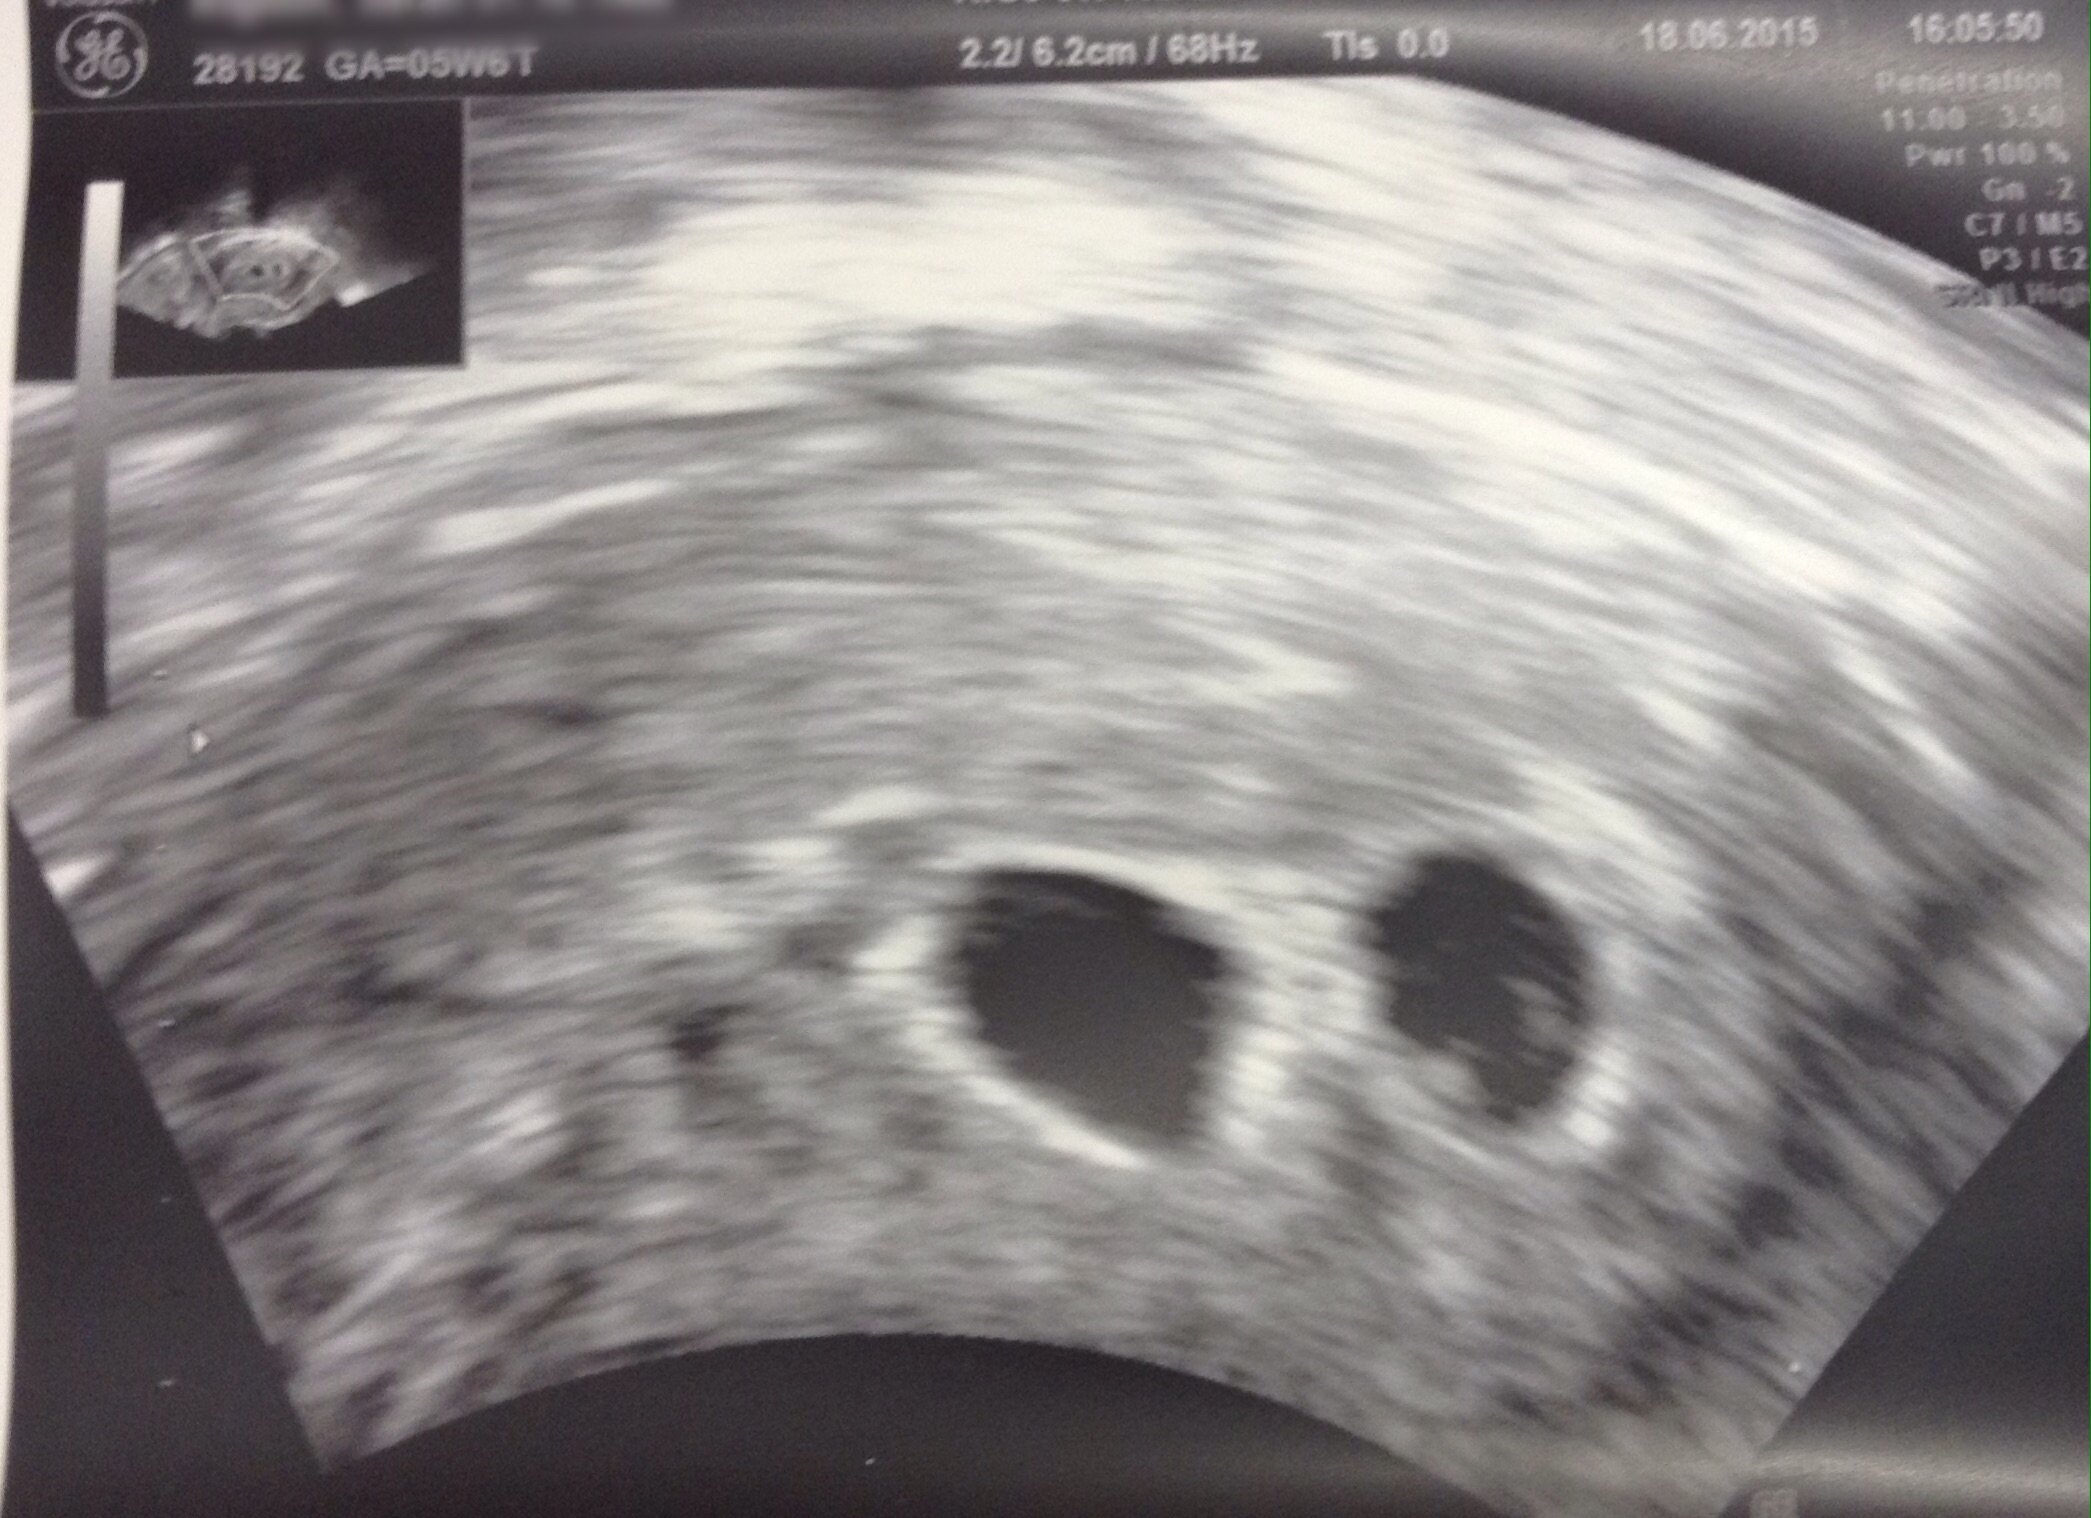

I know it is still early but some of you have already had your first ultrasound.

Feel free to share your picture(s) as you have them done!

Also be sure to include any information related to the U/S that you want to share with the group (how many weeks, heart rate, type of U/S, etc.).

Anyone else get an abdominal ultrasound for their first?